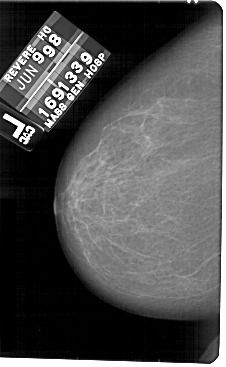

A_1816_1.RIGHT_CC

RIGHT_MLO LINES 5491 PIXELS_PER_LINE 3361 BITS_PER_PIXEL 12 RESOLUTION 43.5 OVERLAY